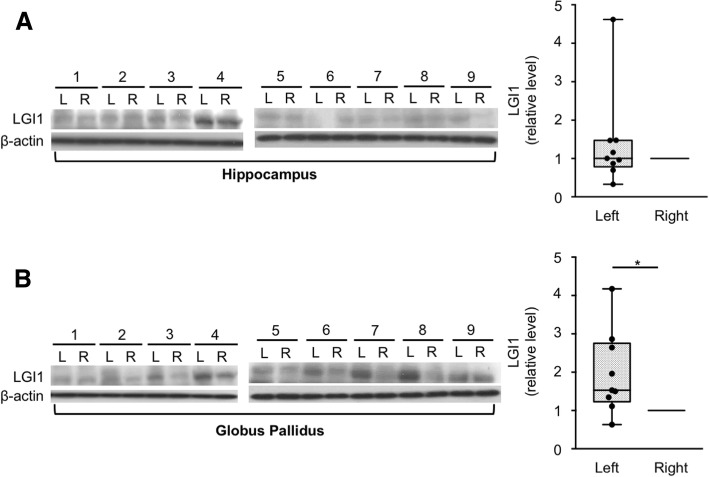

Given the asymmetric clinical and radiological features, we sought to determine whether the LGI1 expression is different between the left and right hemispheres. A total of 36 tissue sections from nine autopsy brains (one hippocampus and one globus pallidus tissues from each hemisphere) were obtained from two brain banks (Additional file 1: Table S2). Five of the nine brains were from right-handed donators, and four were without handedness information. In the neuropathology, seven of the nine brains were normal, one showed incidental changes consistent with aging, and one had hypoxic change without an asymmetrical feature in the cerebrum.

In the hippocampus, the western blotting and optical density analysis revealed no significant difference in LGI1 expression between both hemispheres (relative LGI1 expression of left/right = 1.39 ± 1.26, P = 0.653, Fig. 2a). Four left hemisphere hippocampus showed higher expressions of LGI1 than their right hippocampus (4/9, 44.44%, in sample nos. 1, 5, 8, and 9).

Fig. 2.

Hemispheric asymmetry of LGI1 expression in the human brain samples. a In the hippocampus, the western blotting and optical density analysis revealed no significant difference in LGI1 expression between both hemispheres (relative LGI1 expression of left/right = 1.39 ± 1.26, P = 0.653). Four samples (1, 5, 8, and 9) had higher LGI1 expression on the left side. b In the globus pallidus, the LGI1 expression was significantly increased on the left hemisphere (relative LGI1 expression of left/right = 1.97 ± 1.08, P = 0.019). All samples, except one (1), had higher LGI1 expression on the left side. The box plots show the median (line), interquartile ranges (boxes), and minimum to maximum (whiskers). P values were calculated using Wilcoxon matched pairs signed-rank test. *P < 0.05

However, in the globus pallidus, the LGI1 expression was significantly increased on the left hemisphere (relative LGI1 expression of left/right = 1.97 ± 1.08, P = 0.019, Fig. 2b). Eight left globus pallidus samples (8/9, 88.89%, in sample nos. 2, 3, 4, 5, 6, 7, 8, and 9) showed higher expressions of LGI1 compared to their right globus pallidus. This result suggested that the LGI1 expression is asymmetric (left > right) in the human brain.